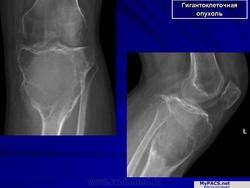

Рентгенологическое исследование гигантоклеточной опухоли показывает, что гигантоклеточиая опухоль локализуется в эпифизе и распространяется на метаэпифизарную часть кости. Поражение носит литический характер, имеет четкие контуры и умеренно или слабо контрастные костные балки. На границе метафиза контуры новообразования менее четкие, чем на остальном протяжении. Склеротические изменения вокруг опухоли развиваются редко, а такие угрожающие признаки, как козырек Кодмена или «лучистый венец», очень редки. Многие гигантоклеточные опухоли не выходят за пределы пораженной кости, но иногда они прорастают кортикальный слой и выходят в мягкие ткани, где покрываются тонким слоем новообразованной кости, едва заметкой при рентгенологическом исследовании. Такие же новообразования кости в виде «яичной скорлупы» имеются в имплантатах опухоли в мягких тканях и в метастазах в легких. Некоторые исследователи различают три стадии развития гигантоклеточной опухоли. На первой стадии узел небольшой, бессимптомный и не выходит за пределы пораженной кости. Вторая стадия документируется довольно объемным новообразованием, вплотную подходящим к наружному контуру кости. На третьей стадии опухоль проявляет агрессивные свойства и дает яркую клиническую симптоматику, связанную с се быстрым ростом и возникновением патологического перелома. На компьютерной томограмме отмечаются деструкция кортикального и медуллярного слоев и проникновение опухоли в окружающие мягкие ткани.

Обычно в пораженном метафизе располагается овальный очаг разрежения, кортикальный слой на его уровне истончен, кость «вздута». При небольшом распространении опухоль располагается несколько эксцентрично, а при обширном поражении — центрально.

При агрессивном течении процесса кортикальный слой истончается до толщины папиросной бумаги, а иногда разрушается. Остеопороз отсутствует. Структура очага крупноячеистая, а при литической форме однородно просветленная. Разрушения суставного хряща не наблюдается.

Остеобластокластома (ячеистая форма) дистального эпиметафиза лучевой кости

а — прямая проекция;

б — боковая проекция.

Дистальный конец лучевой кости умеренно «вздут», преимущественно в ладонно-локтевую сторону. Корковый слой кости на этом уровне значительно истончен, но всюду сохранен; контуры его крупноволнистые. Структура «вздутого» участка имеет крупноячеистый рисунок. Дифференциальная диагностика остеобластокластомы с костной кистой трудна и базируется в основном на клинических данных. Для кисты характерно более спокойное, безболезненное течение. Решающее значение имеет костная пункция.